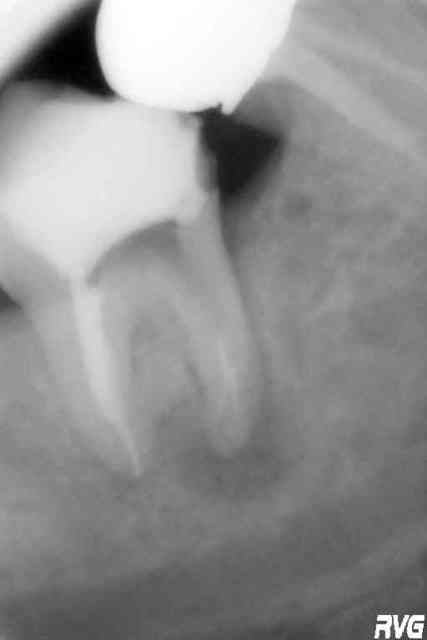

radios

R1 uq8spw - Eugenol

R2 hscwt1 - Eugenol

R3 bceowk - Eugenol

R4 vrw98y - Eugenol